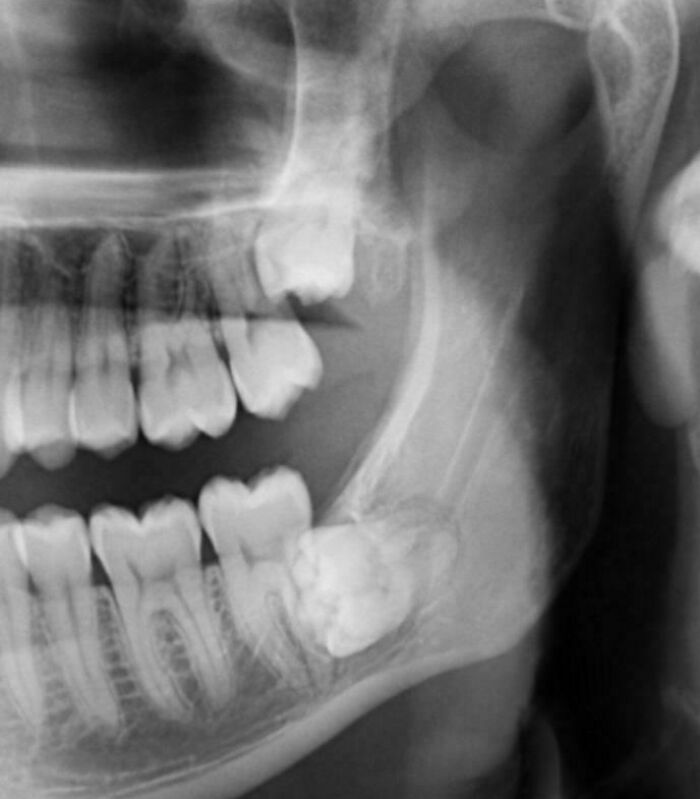

#6 Minulý mesiac som išiel na dentálnu hygienu a spomenul som pocit znecitlivenia v zube – bol som šokovaný, keď som zistil, že mi nádor požiera čeľustnú kosť